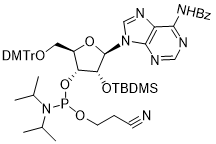

馬鞍山致研生物醫(yī)藥科技有限公司成立于馬鞍山市鄭浦港新區(qū)現(xiàn)代產(chǎn)業(yè)園。公司專(zhuān)注于生物小分子、醫(yī)藥中間體相關(guān)產(chǎn)品的研發(fā)和生產(chǎn),產(chǎn)品主要包括DNA亞磷酰胺單體、RNA亞磷酰胺單體、特殊單體以及按照客戶(hù)要求定制的RNA和DNA,并且公司提供定制合成等方面的研究服...

馬鞍山致研生物醫(yī)藥科技有限公司成立于馬鞍山市鄭浦港新區(qū)現(xiàn)代產(chǎn)業(yè)園。公司專(zhuān)注于生物小分子、醫(yī)藥中間體相關(guān)產(chǎn)品的研發(fā)和生產(chǎn),產(chǎn)品主要包括DNA亞磷酰胺單體、RNA亞磷酰胺單體、特殊單體以及按照客戶(hù)要求定制的RNA和DNA,并且公司提供定制合成等方面的研究服...